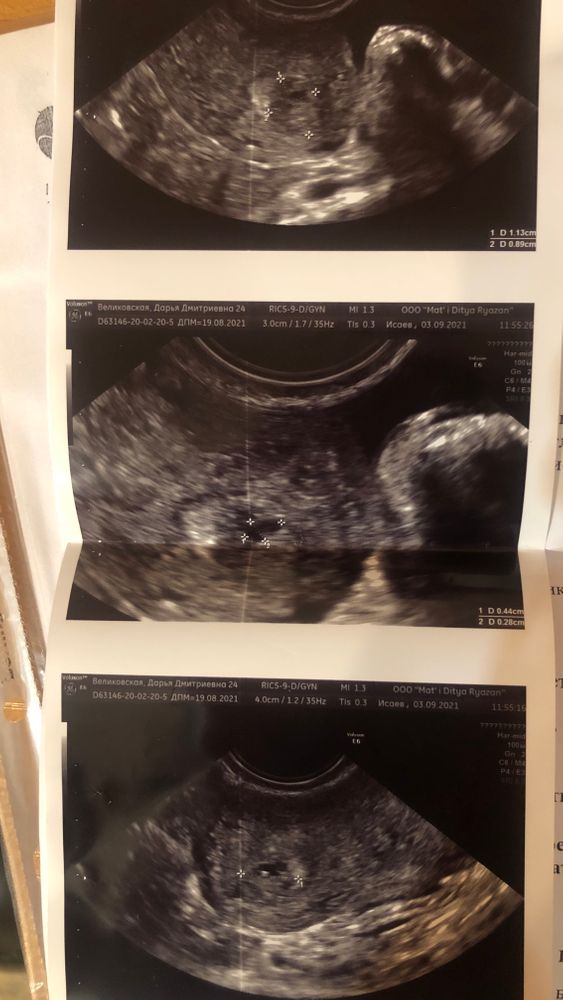

Ангелина, нет, кровотока там нет. То есть это образование не растет из матки, а как бы плавает в ней что ли. Изображение

Катюнечка Солнышко, мы с ним договорились на ноябрь, чтобы больше времени прошло и больше было шансов на то, что все выйдет. Так как он считает, что это просто сгусточек плавает. Он не видит там кровоток и того, что это растет из полости матки. а перед месячными смысла идти нет, строго на 8-9 дц. Но я думаю дотерплю до ноября, если не будет ничего критичного…